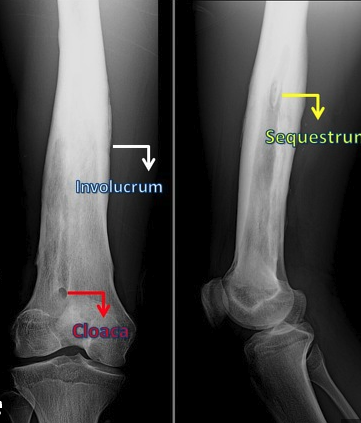

Classic DDx for Osseous Sequestrum

Osteomyelitis

Lymphoma

Fibrosarcoma

EG